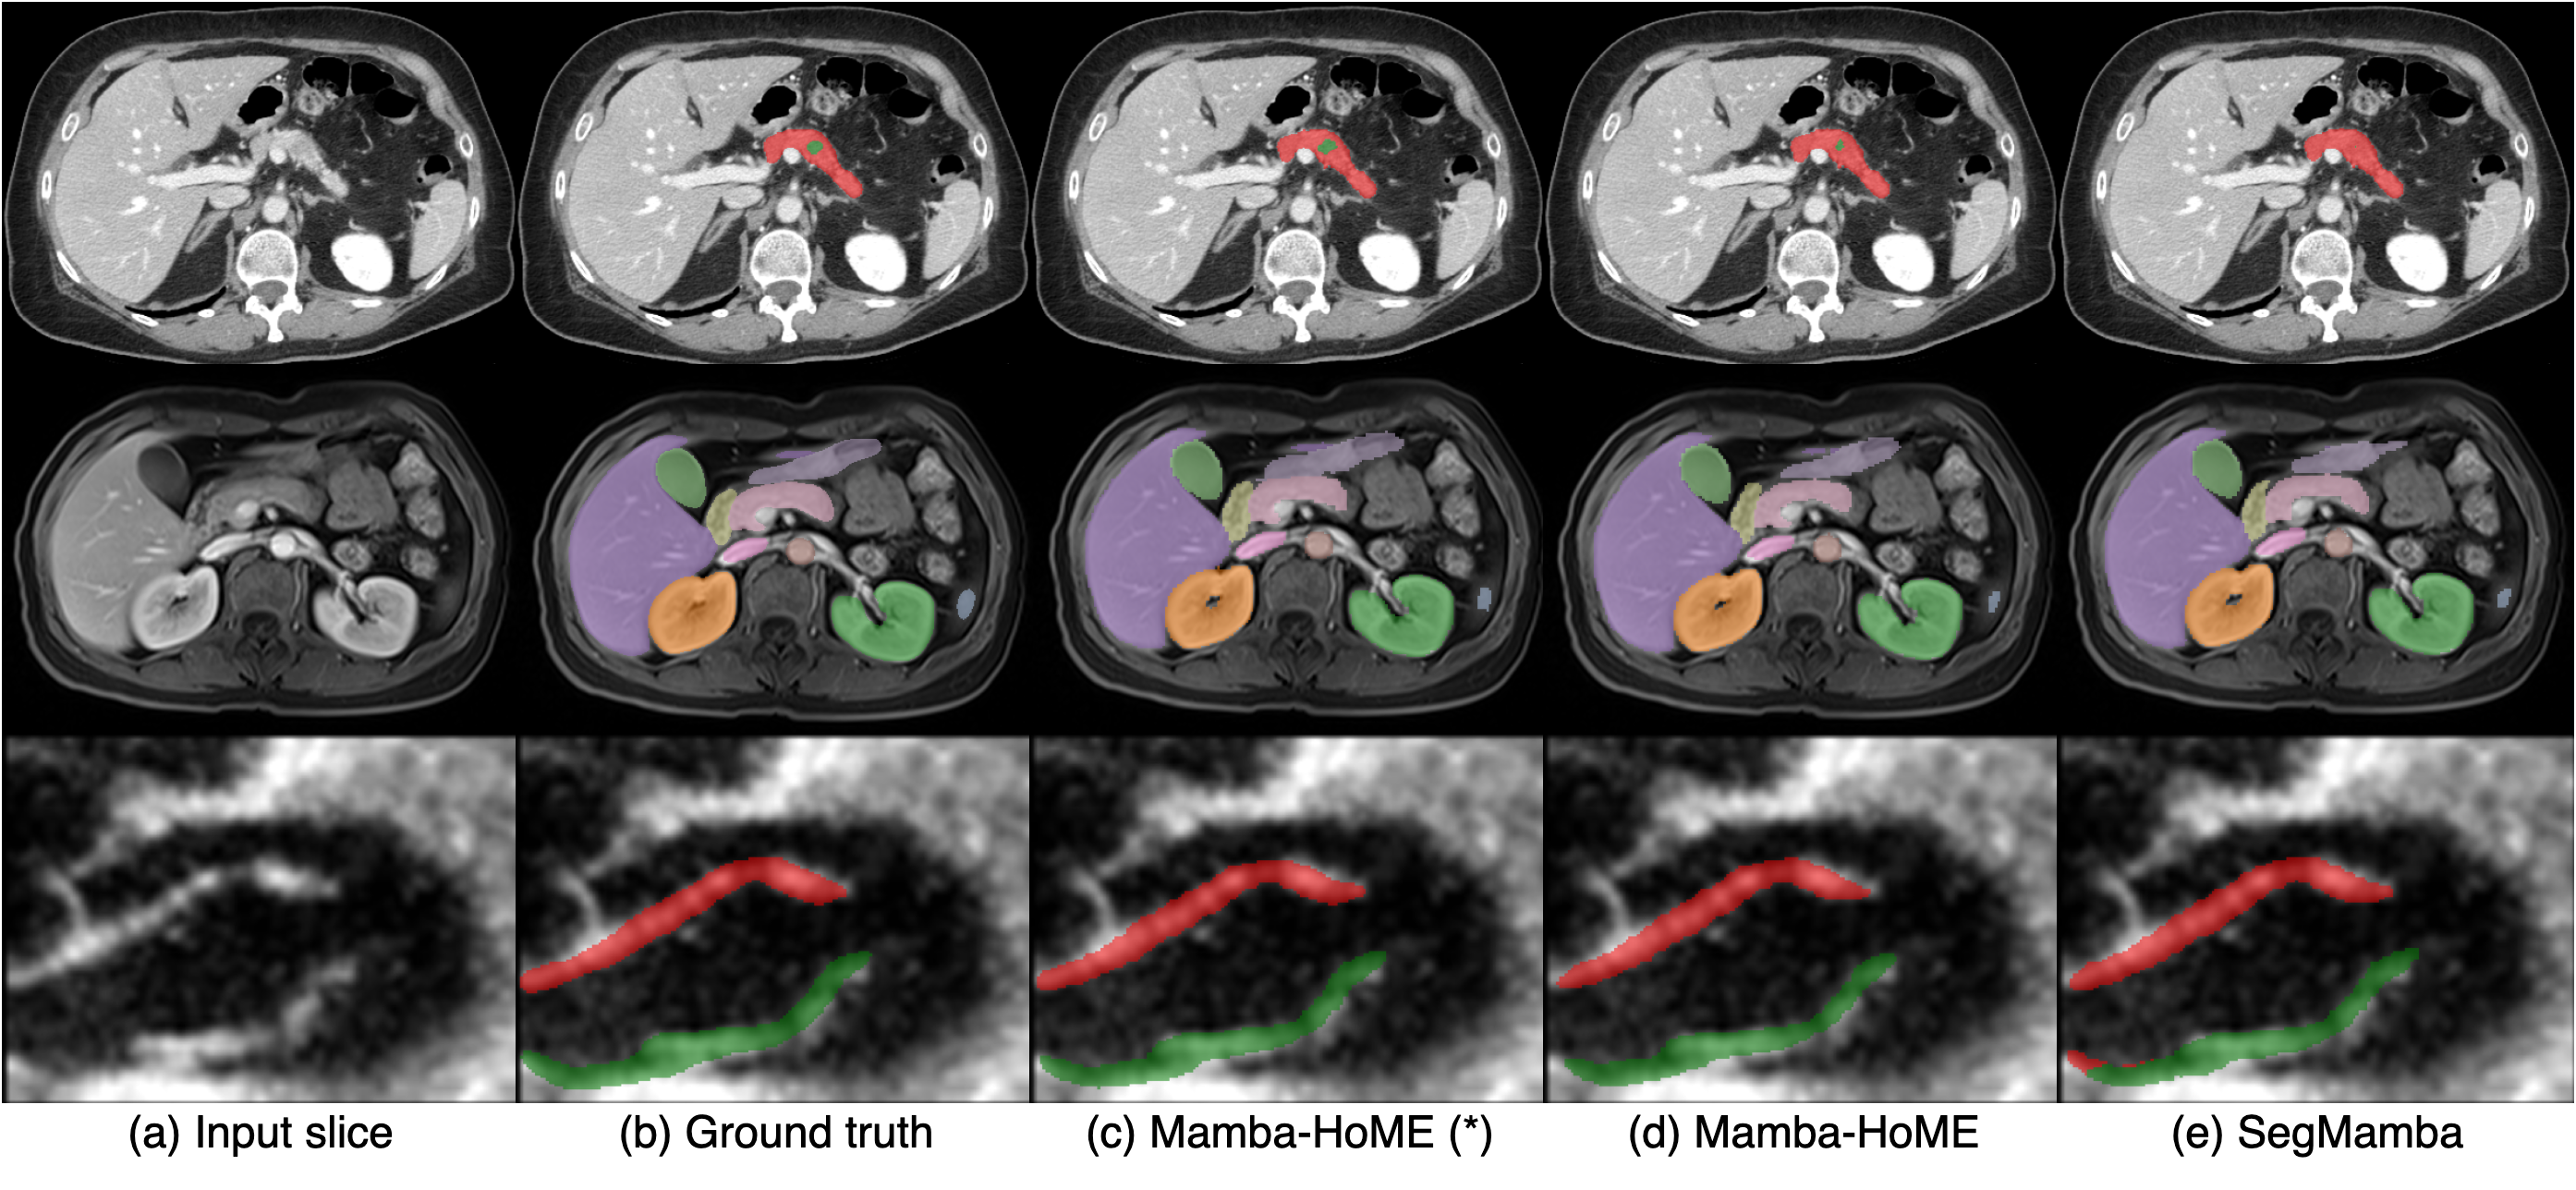

This adaptability highlights Mamba-HoME’s ability to mitigate challenges posed by variations in modality, resolution, and clinical context. Moreover, its consistently high performance across heterogeneous datasets underscores its potential for practical deployment, where robust, modality-agnostic feature representations and precise segmentation are essential for scalable, real-world medical imaging applications. As shown in Figure 3, supervised pre-training significantly improves Mamba-HoME’s performance compared to training from scratch or baseline methods, reducing artifacts and enhancing boundary segmentation for objects of varying sizes across the three primary 3D medical imaging modalities.

Refer to caption

Figure 3: Qualitative segmentation results from top to bottom: CT, MRI, and 3D US. From left to right, each column shows the input slice, ground truth, our proposed pre-trained Mamba-HoME, Mamba-HoME trained from scratch, and the baseline SegMamba.